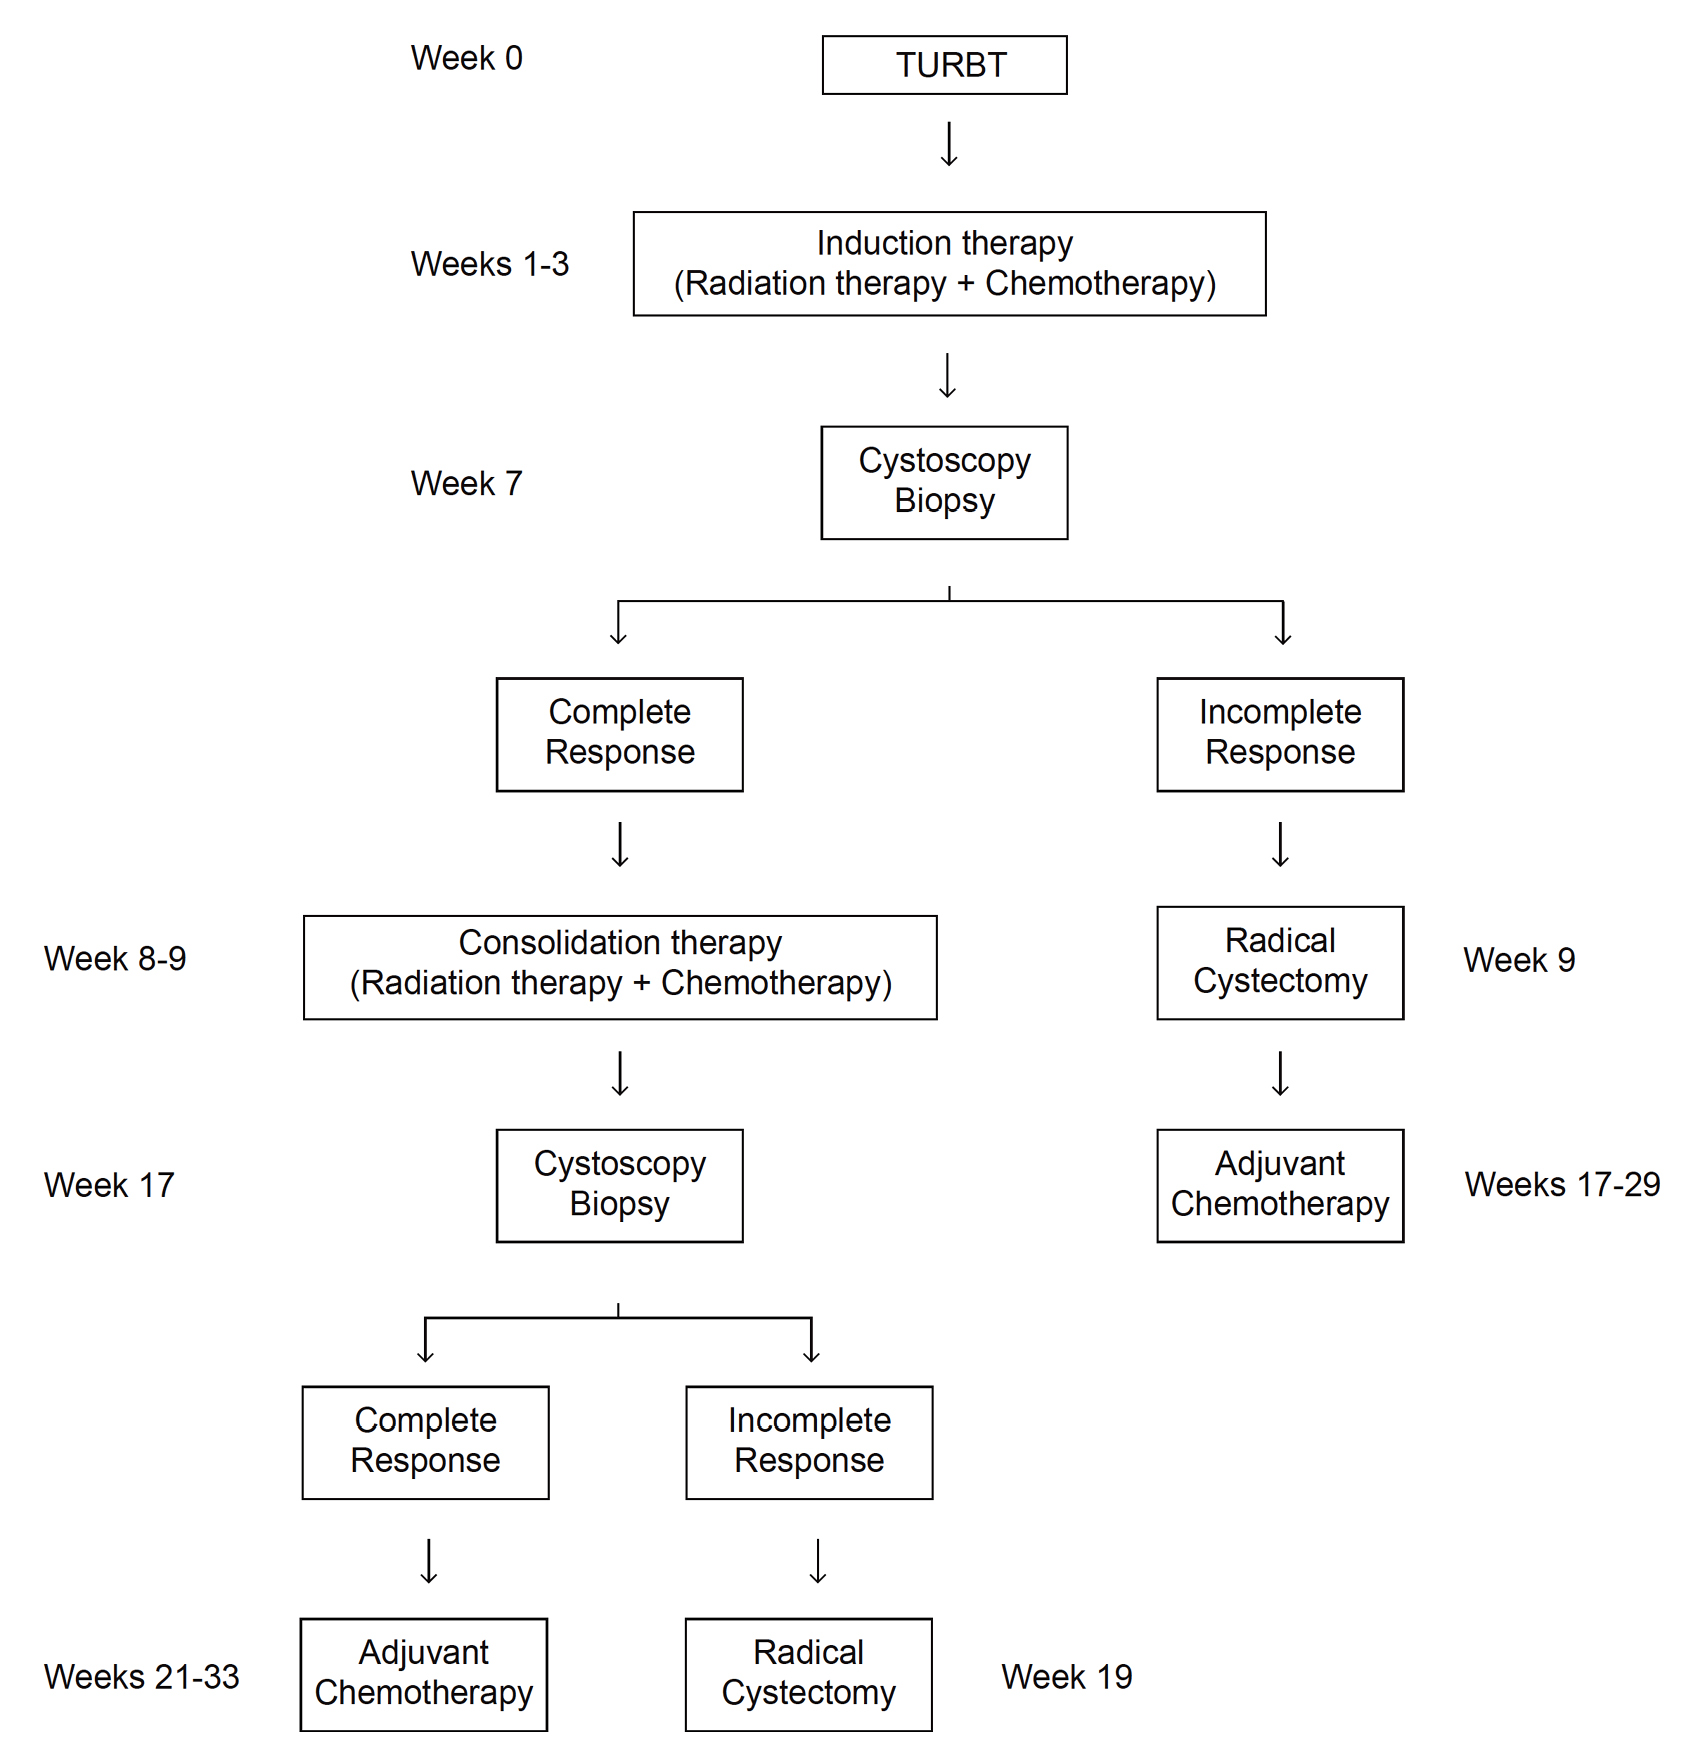

Bladder preservation in the treatment of muscle-invasive bladder cancer

Abstract 153 | HTML Downloads 59 PDF Downloads 66 | DOI https://doi.org/10.14440/bladder.2014.37Page e5